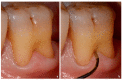

Various classification systems have been proposed to describe furcation lesions and Glickman's classification for many years seems to have been the most widely utilized in the sole clinical diagnosis with no reference to the prognostic value of the lesion itself. This article reviews the previous classification systems and proposes a new method to classify furcation lesions based on the position of the gingival margin and its relationship with the furcation area (clinically exposed/non-exposed furcation area) providing significant aid for a better understanding of furcation involvements and increases the prognostic value of treatments in the long term.